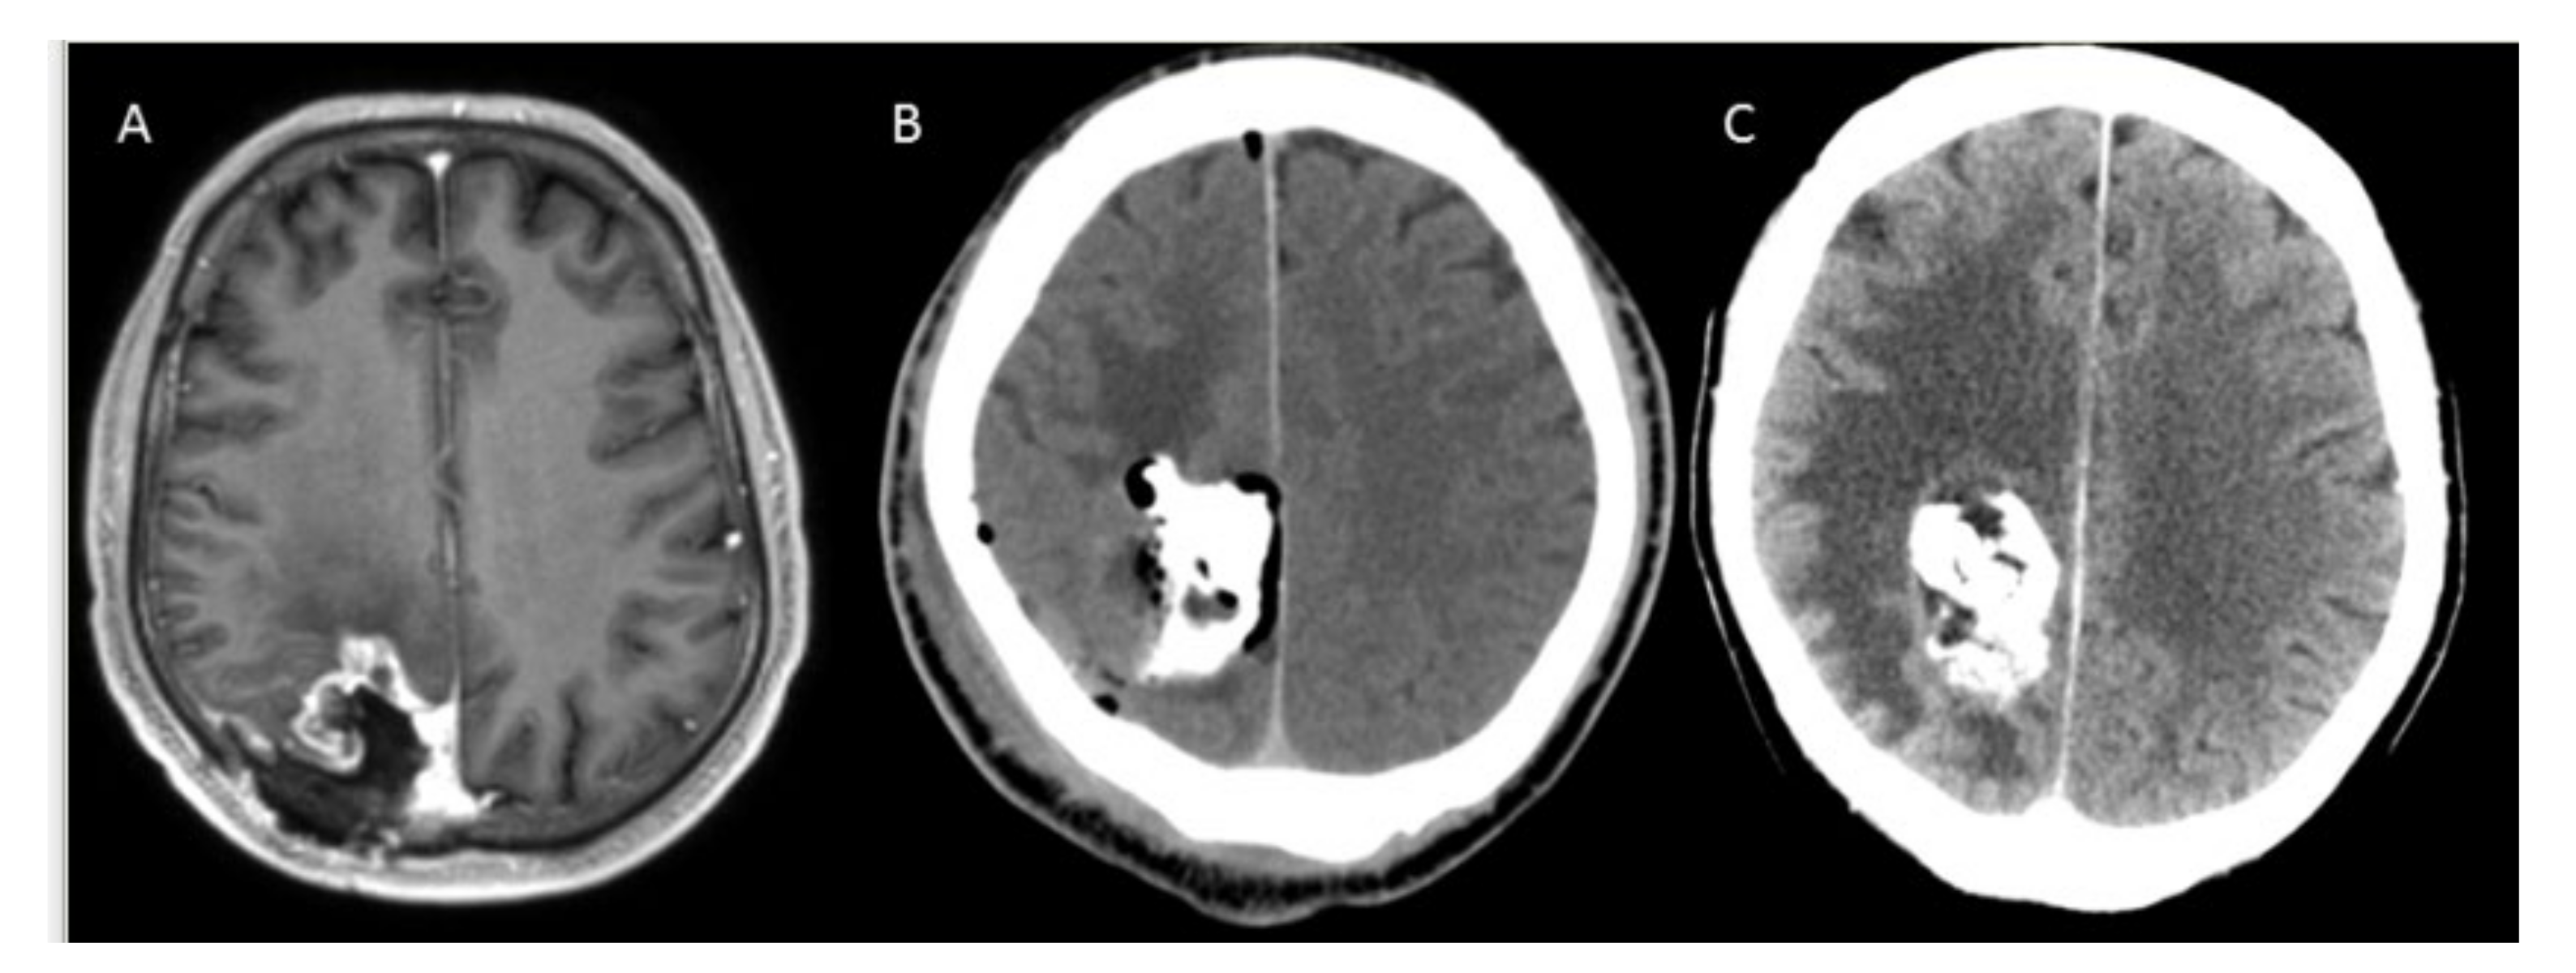

3.2. Safety and Complications